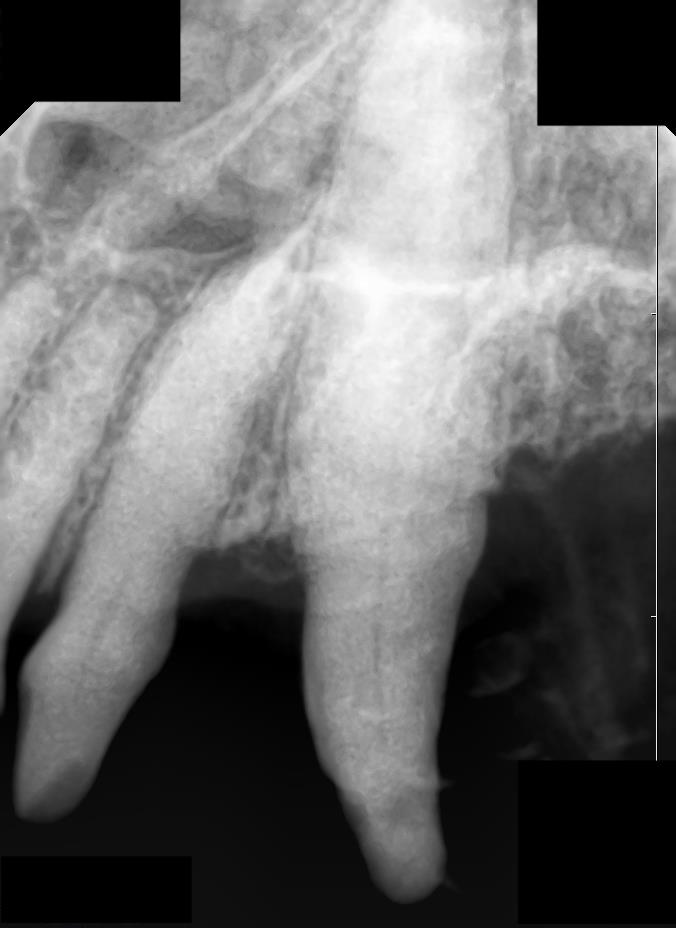

肉眼的に歯の表面の異常を確認します。

疑わしい場合は歯科レントゲンにてエナメル質の損傷程度を評価します。